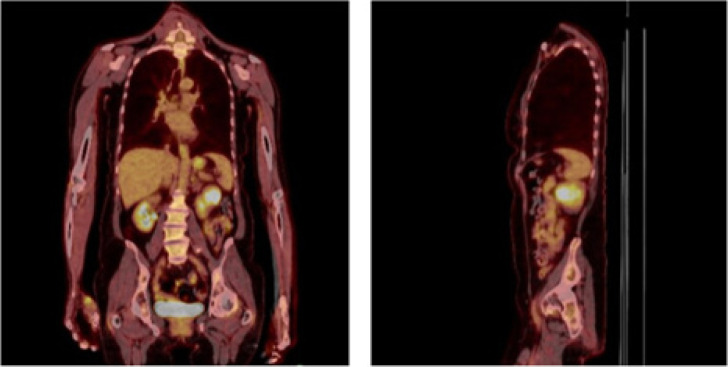

Adenoid cystic carcinoma (ACC) is a rare tumor, accounting for 1% of all head and neck cancers, with an aggressive nature characterized by local recurrence, delayed metastasis, and survival of less than 50% at 10 years. This is a case of biopsy-proven ACC to the kidney, 1 of 29 known occurrences, managed by metastasectomy by robotic-assisted nephrectomy, with plans for resection of lung metastasis. Thirteen years after diagnosis of sinonasal ACC treated with resection, the patient presented with shortness of breath. This prompted a CT scan of the chest, which led to the incidental finding of left renal mass and pulmonary lesion. Literature suggests improved disease-specific survival in locoregional recurrence treated with surgery versus radiation; in patients with metastasis to the lung, metastasectomy offers greater survival benefit than supportive therapy. But, this is not significantly better than chemotherapy or radiation alone. While the optimal therapeutic approach remains to be identified in distant metastatic ACC, metastasectomy remains a viable option for patients who have potentially completely resectable metastatic tumors, appropriate performance status, and adequate affected-organ function. Preoperative counseling should include discussion on partial nephrectomy with prioritization of nephron-sparing but potential for increased perioperative risk versus radical nephrectomy to ensure negative margins and expedite timeline to systemic therapy.

Abstract Image